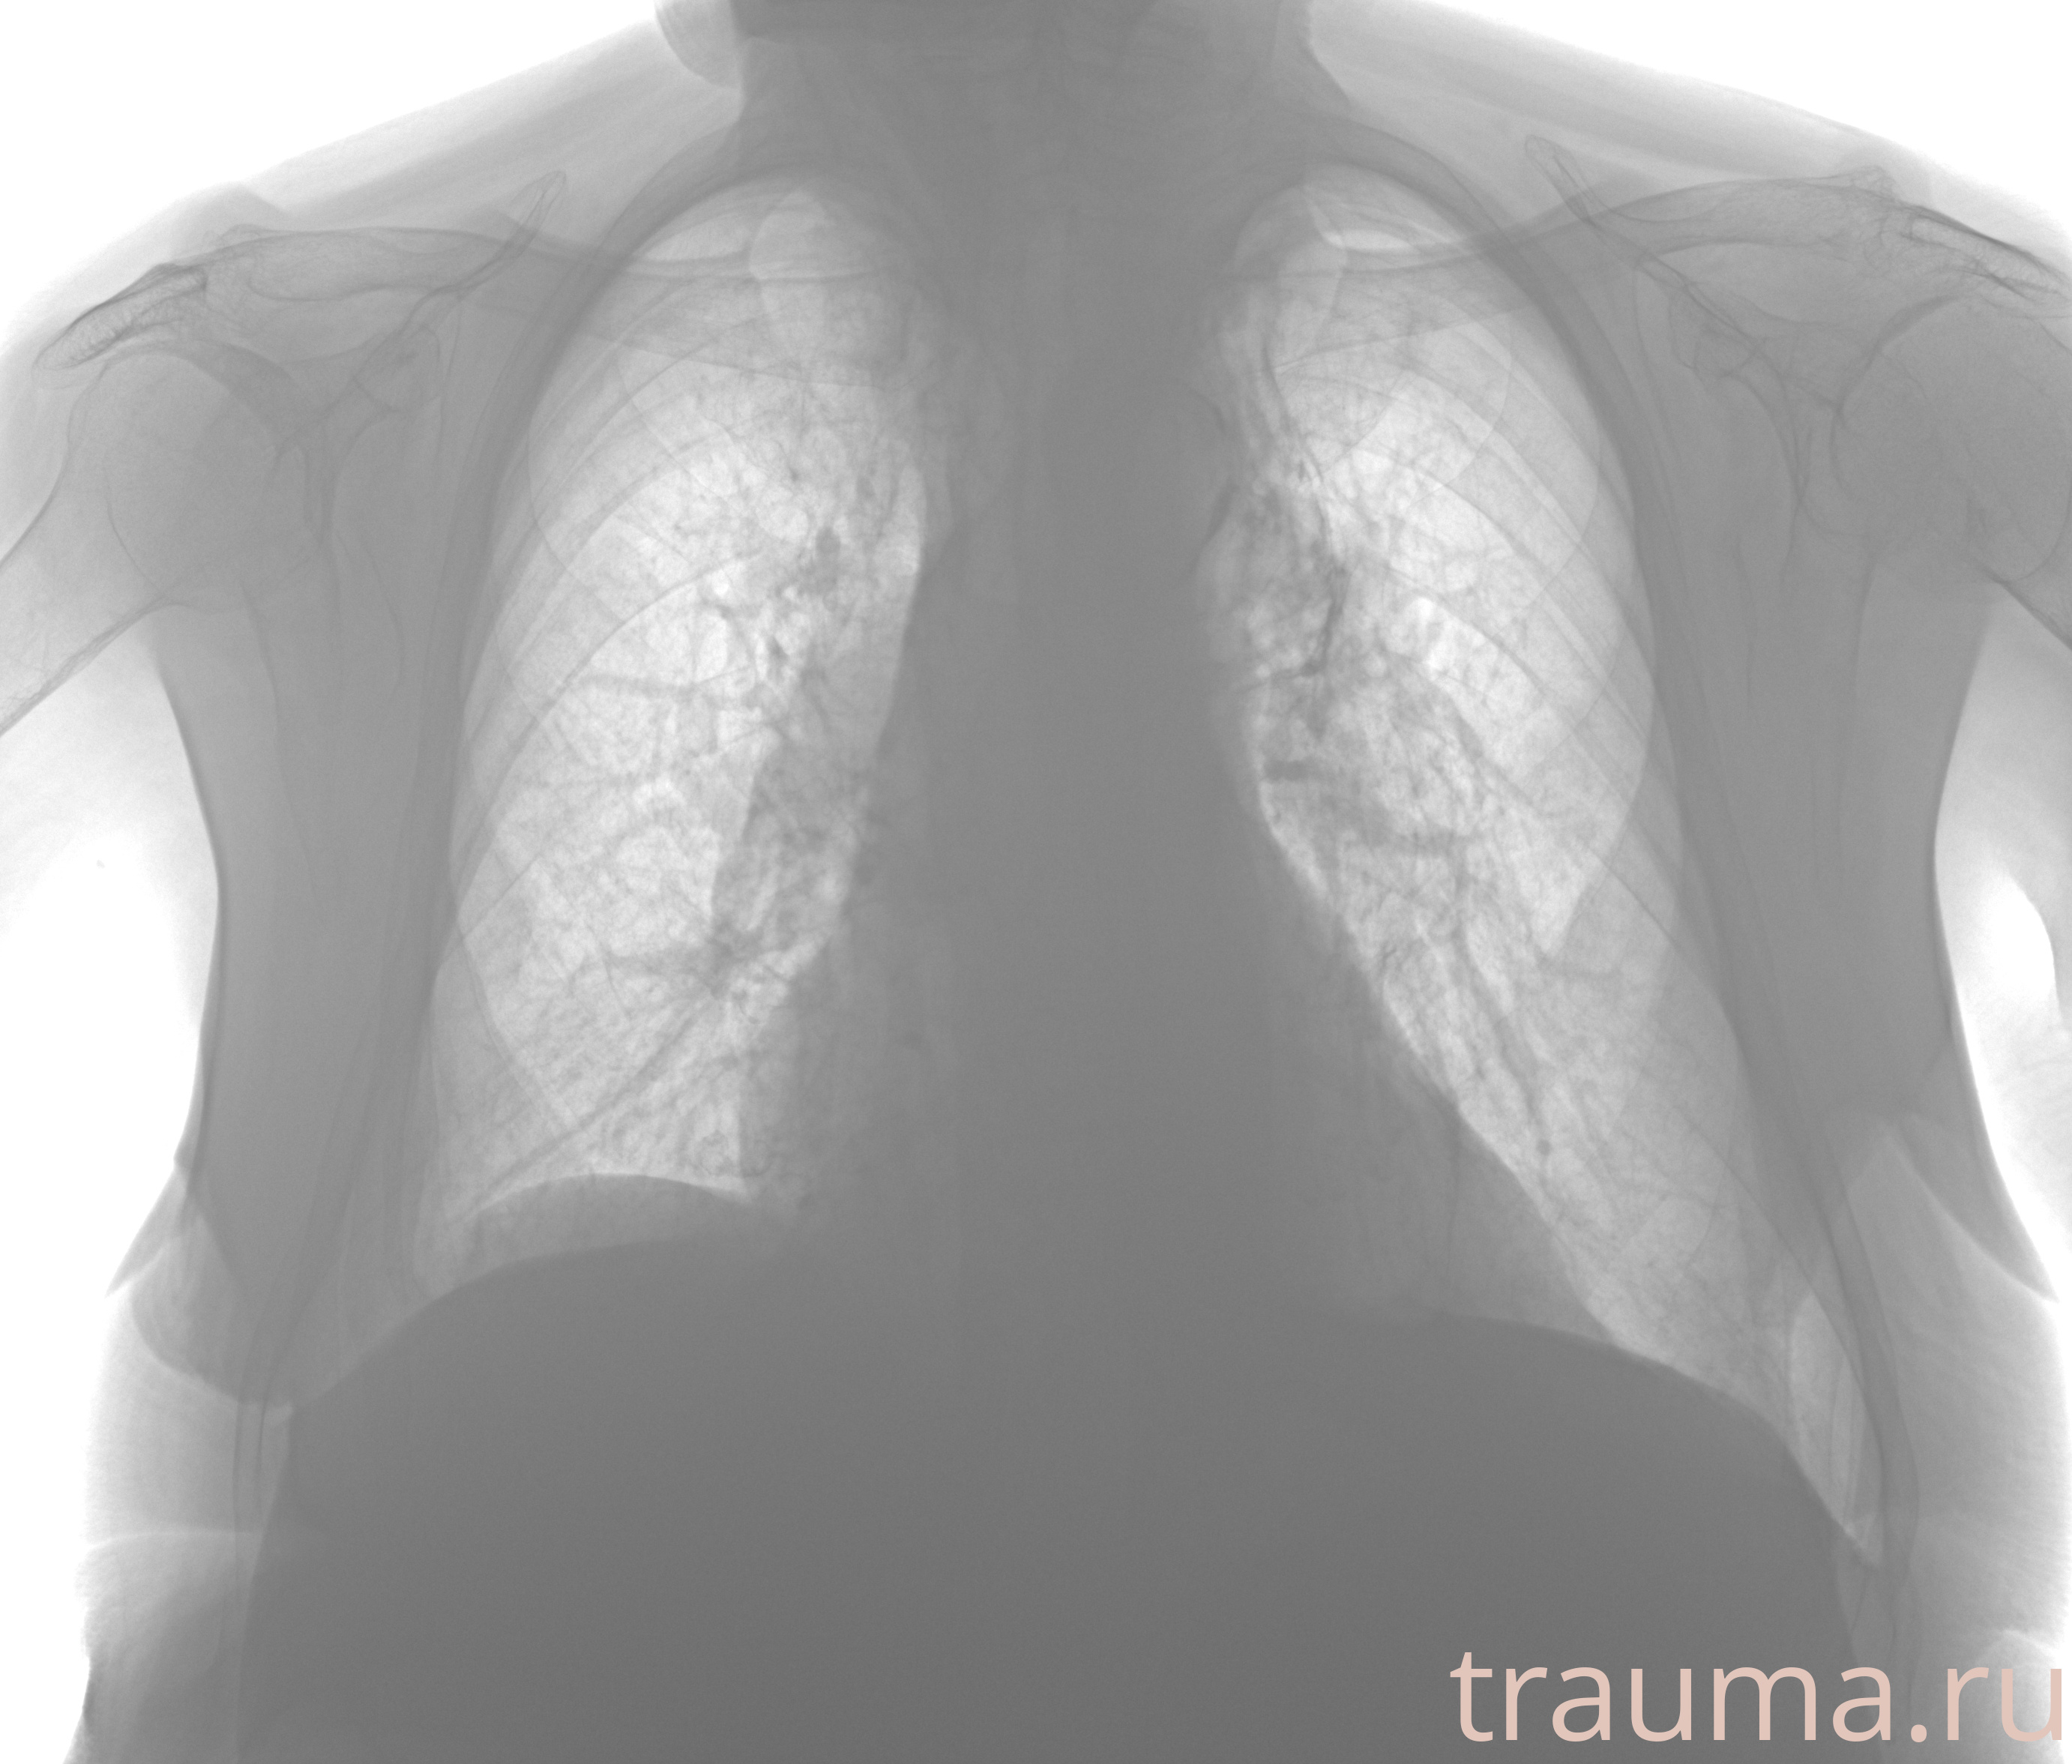

Рентгенограммы

Рентген на дому: по вашему адресу приезжает врач-рентгенолог, травматолог-ортопед с мобильным рентгеновским аппаратом, проводит диагностику травмы или заболевания, делает необходимые рентгенограммы, дает рекомендации по дальнейшему лечению. Получить качественные снимки в домашних условиях возможно благодаря уникальной методике, разработанной МосРентген Центром для института  Склифосовского

Яркость: 1   Контраст: 1   Инвертировать: 0 Увеличение: 1

Перетаскивайте мышь вверх/вниз для контраста, влево/право для яркости. Прокрутка колесом изменяет масштаб. Нажмите Сбросить для возврата к исходному изображению. При увеличении держите мышь в той области, которую хотите рассмотреть.